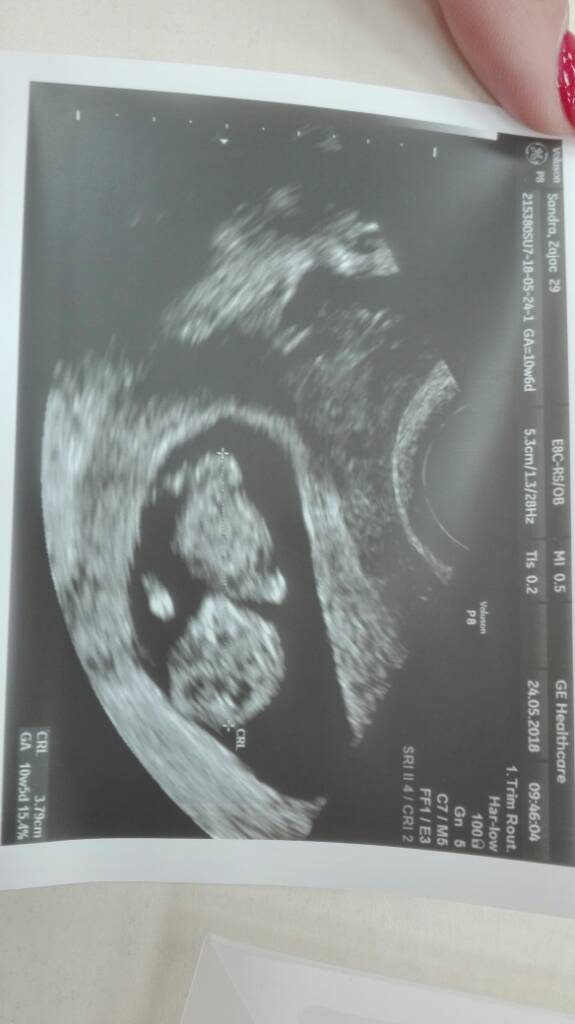

Super...Ja juz po[emoji4][emoji123][emoji123][emoji7][emoji7] Dzidziol ma sie dobrze. Termin zgodny z usg . Mamy 10+6 tyg. Dzidź prawie 4 cm. Doktor mowi ze bardzo ruchliwy. Ale tańcowal [emoji7][emoji7][emoji7][emoji7]Zobacz załącznik 859932